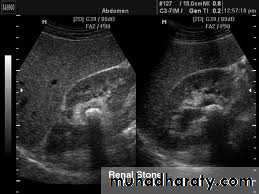

*Stone without hydronephrosis (left) and stone+ hydronephrosis (right) because of dilatation of P.C.S

*Hydronephrosis:-dilated pelvicalyceal system on US